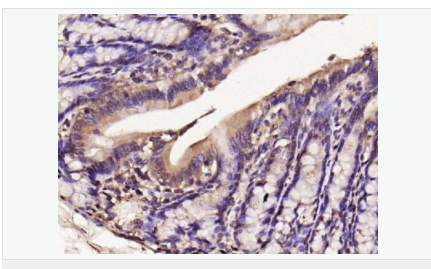

| 产品应用 | WB=1:500-2000 IHC-P=1:100-500 IHC-F=1:100-500 Flow-Cyt=1μg/Test ICC=1:100-500 IF=1:100-500 (石蜡切片需做抗原修复) not yet tested in other applications. optimal dilutions/concentrations should be determined by the end user. |

| 产品介绍 | Nitric oxide (NO) is an inorganic, gaseous free radical that carries a variety of messages between cells. Vasorelaxation, neurotransmission and cytotoxicity can all be potentiated through cellular response to NO. NO production is mediated by members of the nitric oxide synthase (NOS) family. NOS catalyzes the oxidization of L-arginine to produce L-citrulline and NO. Two constitutive isoforms, brain or neuronal NOS (b or nNOS, type I) & endothelial cell NOS (eNOS, type III), and one inducible isoform (iNOS, type II), have been cloned. All NOS isoforms contain calmodulin, nicotinamide adenine dinucleotide phosphate (NADPH), flavin adenine dinucleotide (FAD), and flavin mononucleotide (FMN) binding domains. Nitric oxide synthase is expressed in liver, macrophages, hepatocytes, synoviocytes, stimulated glial cells and smooth muscle cells. Cytokines such as interferon-gamma (IFN), tumor necrosis factor (TNF), interleukin-1 and -2, and lipopolysaccarides (LPS) cause an increase in iNOS mRNA, protein, and activity levels. Protein kinase C-stimulating agents exhibit the same effect on iNOS activity. After cytokine induction, iNOS exhibits a delayed activity response which is then followed by a significant increase in NO production over a long period of time. Human iNOS is regulated by calcium/calmodulin (in contrast with mouse NOS2). Function: Produces nitric oxide (NO) which is a messenger molecule with diverse functions throughout the body. In macrophages, NO mediates tumoricidal and bactericidal actions. Also has nitrosylase activity and mediates cysteine S-nitrosylation of cytoplasmic target proteins such COX2. Subunit: Homodimer. Binds SLC9A3R1. Tissue Specificity: Expressed in the liver, retina, bone cells and airway epithelial cells of the lung. Not expressed in the platelets. Similarity: Belongs to the NOS family. Contains 1 FAD-binding FR-type domain. Contains 1 flavodoxin-like domain. SWISS: P35228 Gene ID: 4843 Database links: Entrez Gene: 4843 Human Entrez Gene: 18126 Mouse Omim: 163730 Human SwissProt: P35228 Human SwissProt: P29477 Mouse Unigene: 709191 Human Unigene: 2893 Mouse Unigene: 10400 Rat Important Note: This product as supplied is intended for research use only, not for use in human, therapeutic or diagnostic applications. 合成与降解(Synthesis and Degradation) 催化生物体内一氧化氮(NO)生成的酶。分神经型一氧化氮合成的酶(nNOS or NOS-1)、诱导型一氧化氮合成的酶(iNOS or NOS-2)、内皮型一氧化氮合成的酶(eNOS or NOS-3)。 |